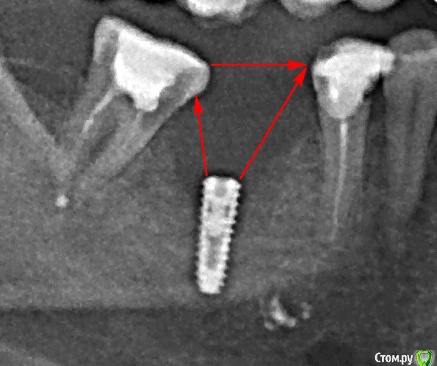

Наталия1966 Опубликовано 25 ноября, 2019 Автор Поделиться Опубликовано 25 ноября, 2019 (изменено) Эта методика больше не помогает?Вы меня подлавливаете, что ль, на словах? Я уже успокоилась, смирилась и с частичным и со всем остальным, как вчера ортопед мне, заметьте МНЕ высказал претензию, что протезировать не может без обточки соседнего зуба, причем таким тоном, что я забыла, что не сама себе вкручивала, что я ему еще приплатить должна за такую установку, что ли в свою челюсть, не в его и не в кого то другого. Почему он не вызвал глав врача, директора, не собрал консилиум, не забил в колокола, не проявил активность в разоблачении проблемы? Перед установкой, когда я высказывала сомнение, что мало высоты кости, что зуба давно не было и так просто раз и все мне вкрутят? Он мне сказал, вот как сейчас помню: "Если бы не было места для зуба, то НИ ОДИН ИМПЛАНТОЛОГ НЕ РЕШИЛСЯ БЫ НА УСТАНОВКУ", да таким тоном сказал, что я господь бога под сомнение ставлю. Теперь он же, через 6 месяцев мне говорит, что места для зуба нет без спила стенки соседнего, ЧТО ЭТО? ЭТО ПОВРЕЖДЕНИЕ, дурдом по простому. Изменено 25 ноября, 2019 пользователем Наталия1966 Ссылка на комментарий